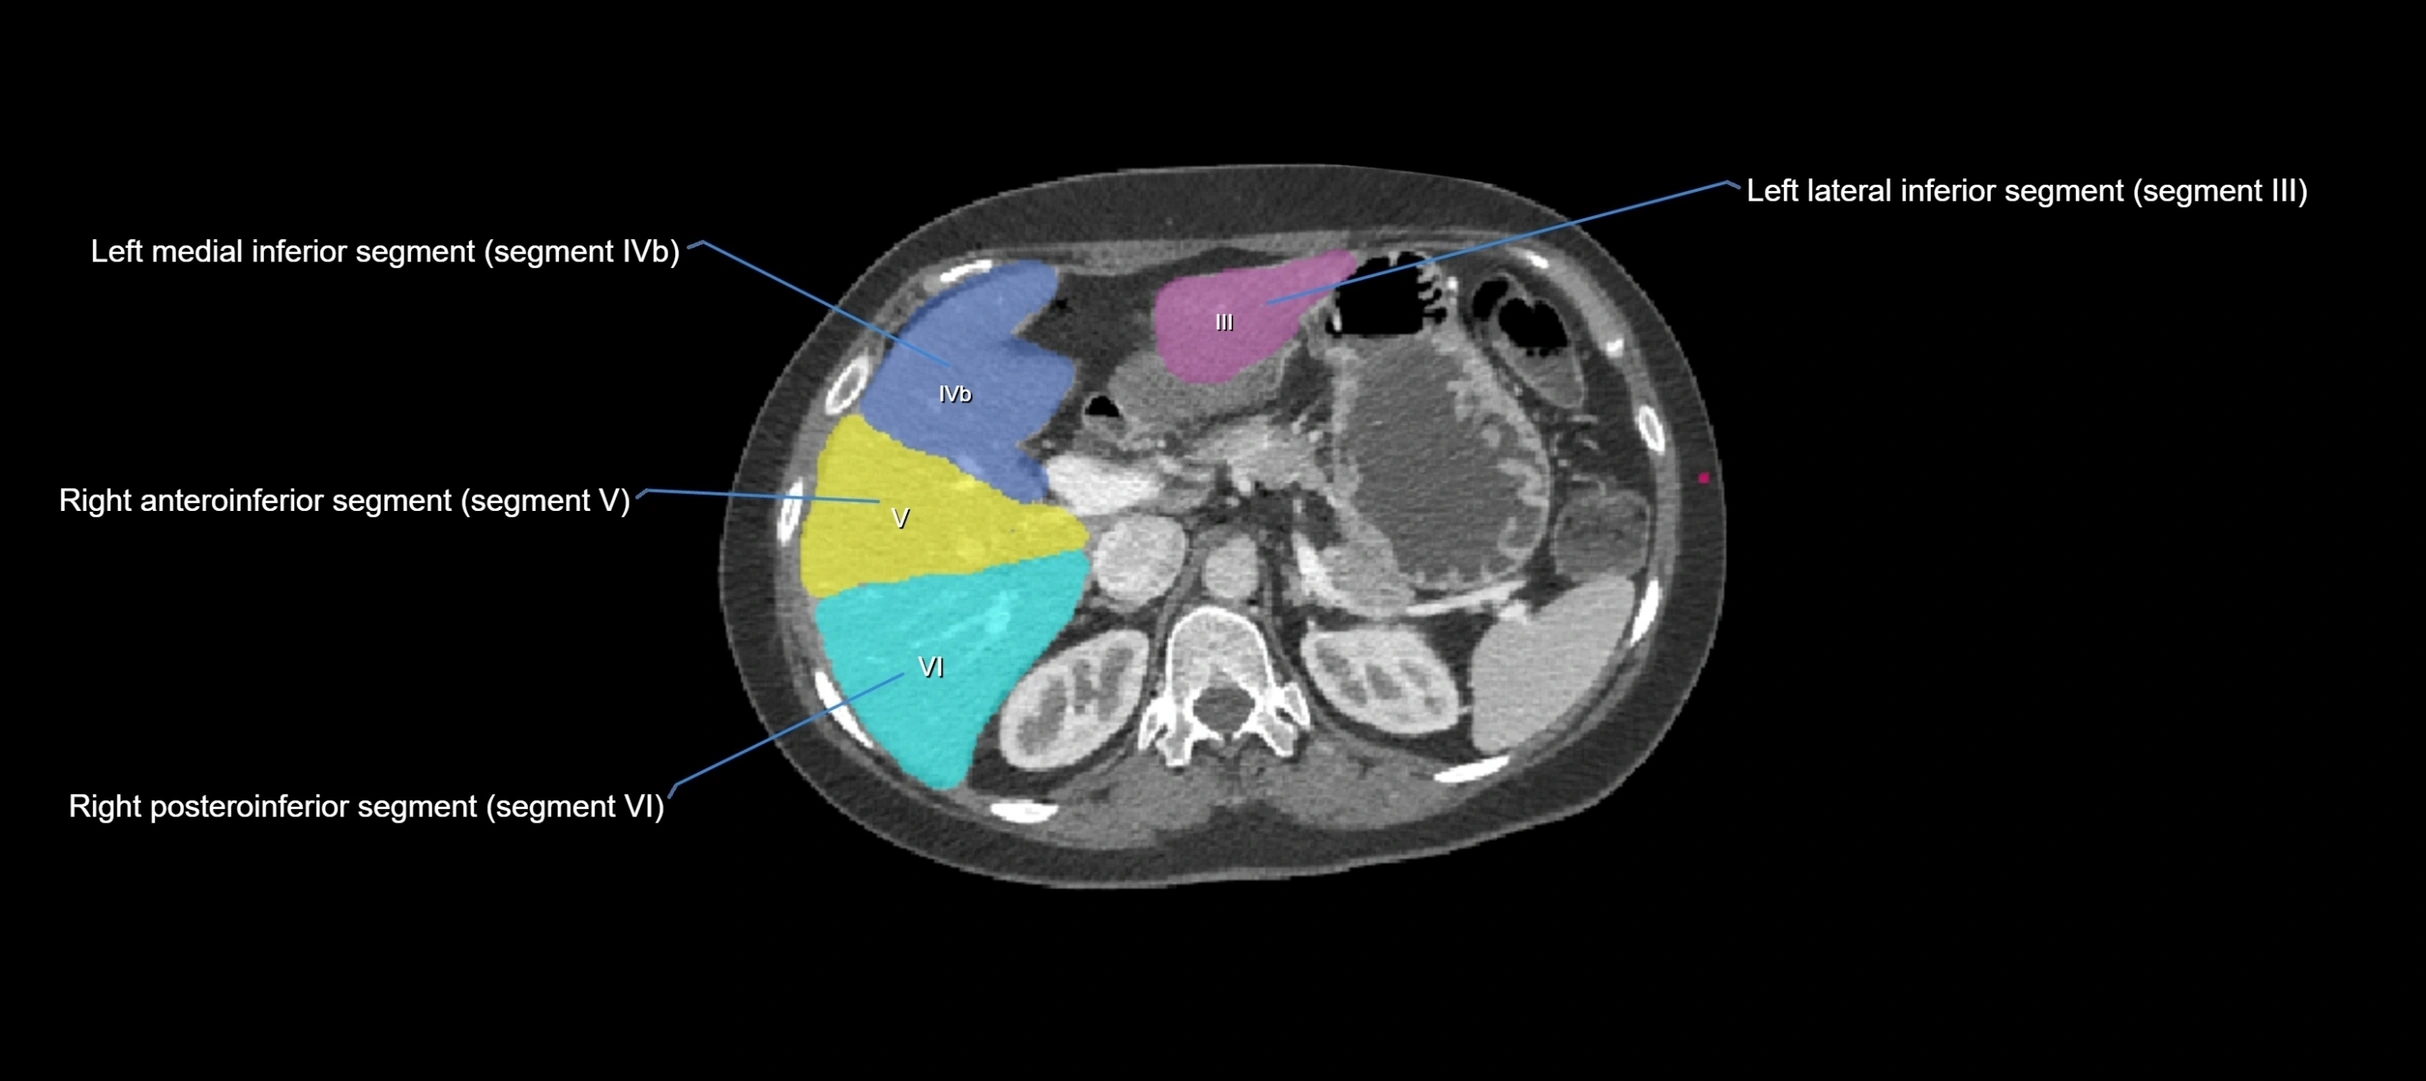

CT Appearance

CT Pre-Contrast:

• Caudate lobe appears as a soft-tissue density, isodense to the rest of the liver

• Enlargement may be appreciated in cirrhosis or Budd–Chiari syndrome

CT Post-Contrast:

• Homogeneous enhancement in the portal venous phase, similar to rest of liver

• Independent venous drainage into the IVC may be visualized

• Lesions follow characteristic CT enhancement patterns (HCC: arterial hyperenhancement with washout; hemangiomas: peripheral nodular enhancement with centripetal fill-in)

CT Venous Phase (functional significance):

• Caudate lobe often enhances relatively more than other lobes in Budd–Chiari syndrome, due to preserved venous outflow

CT Image

image